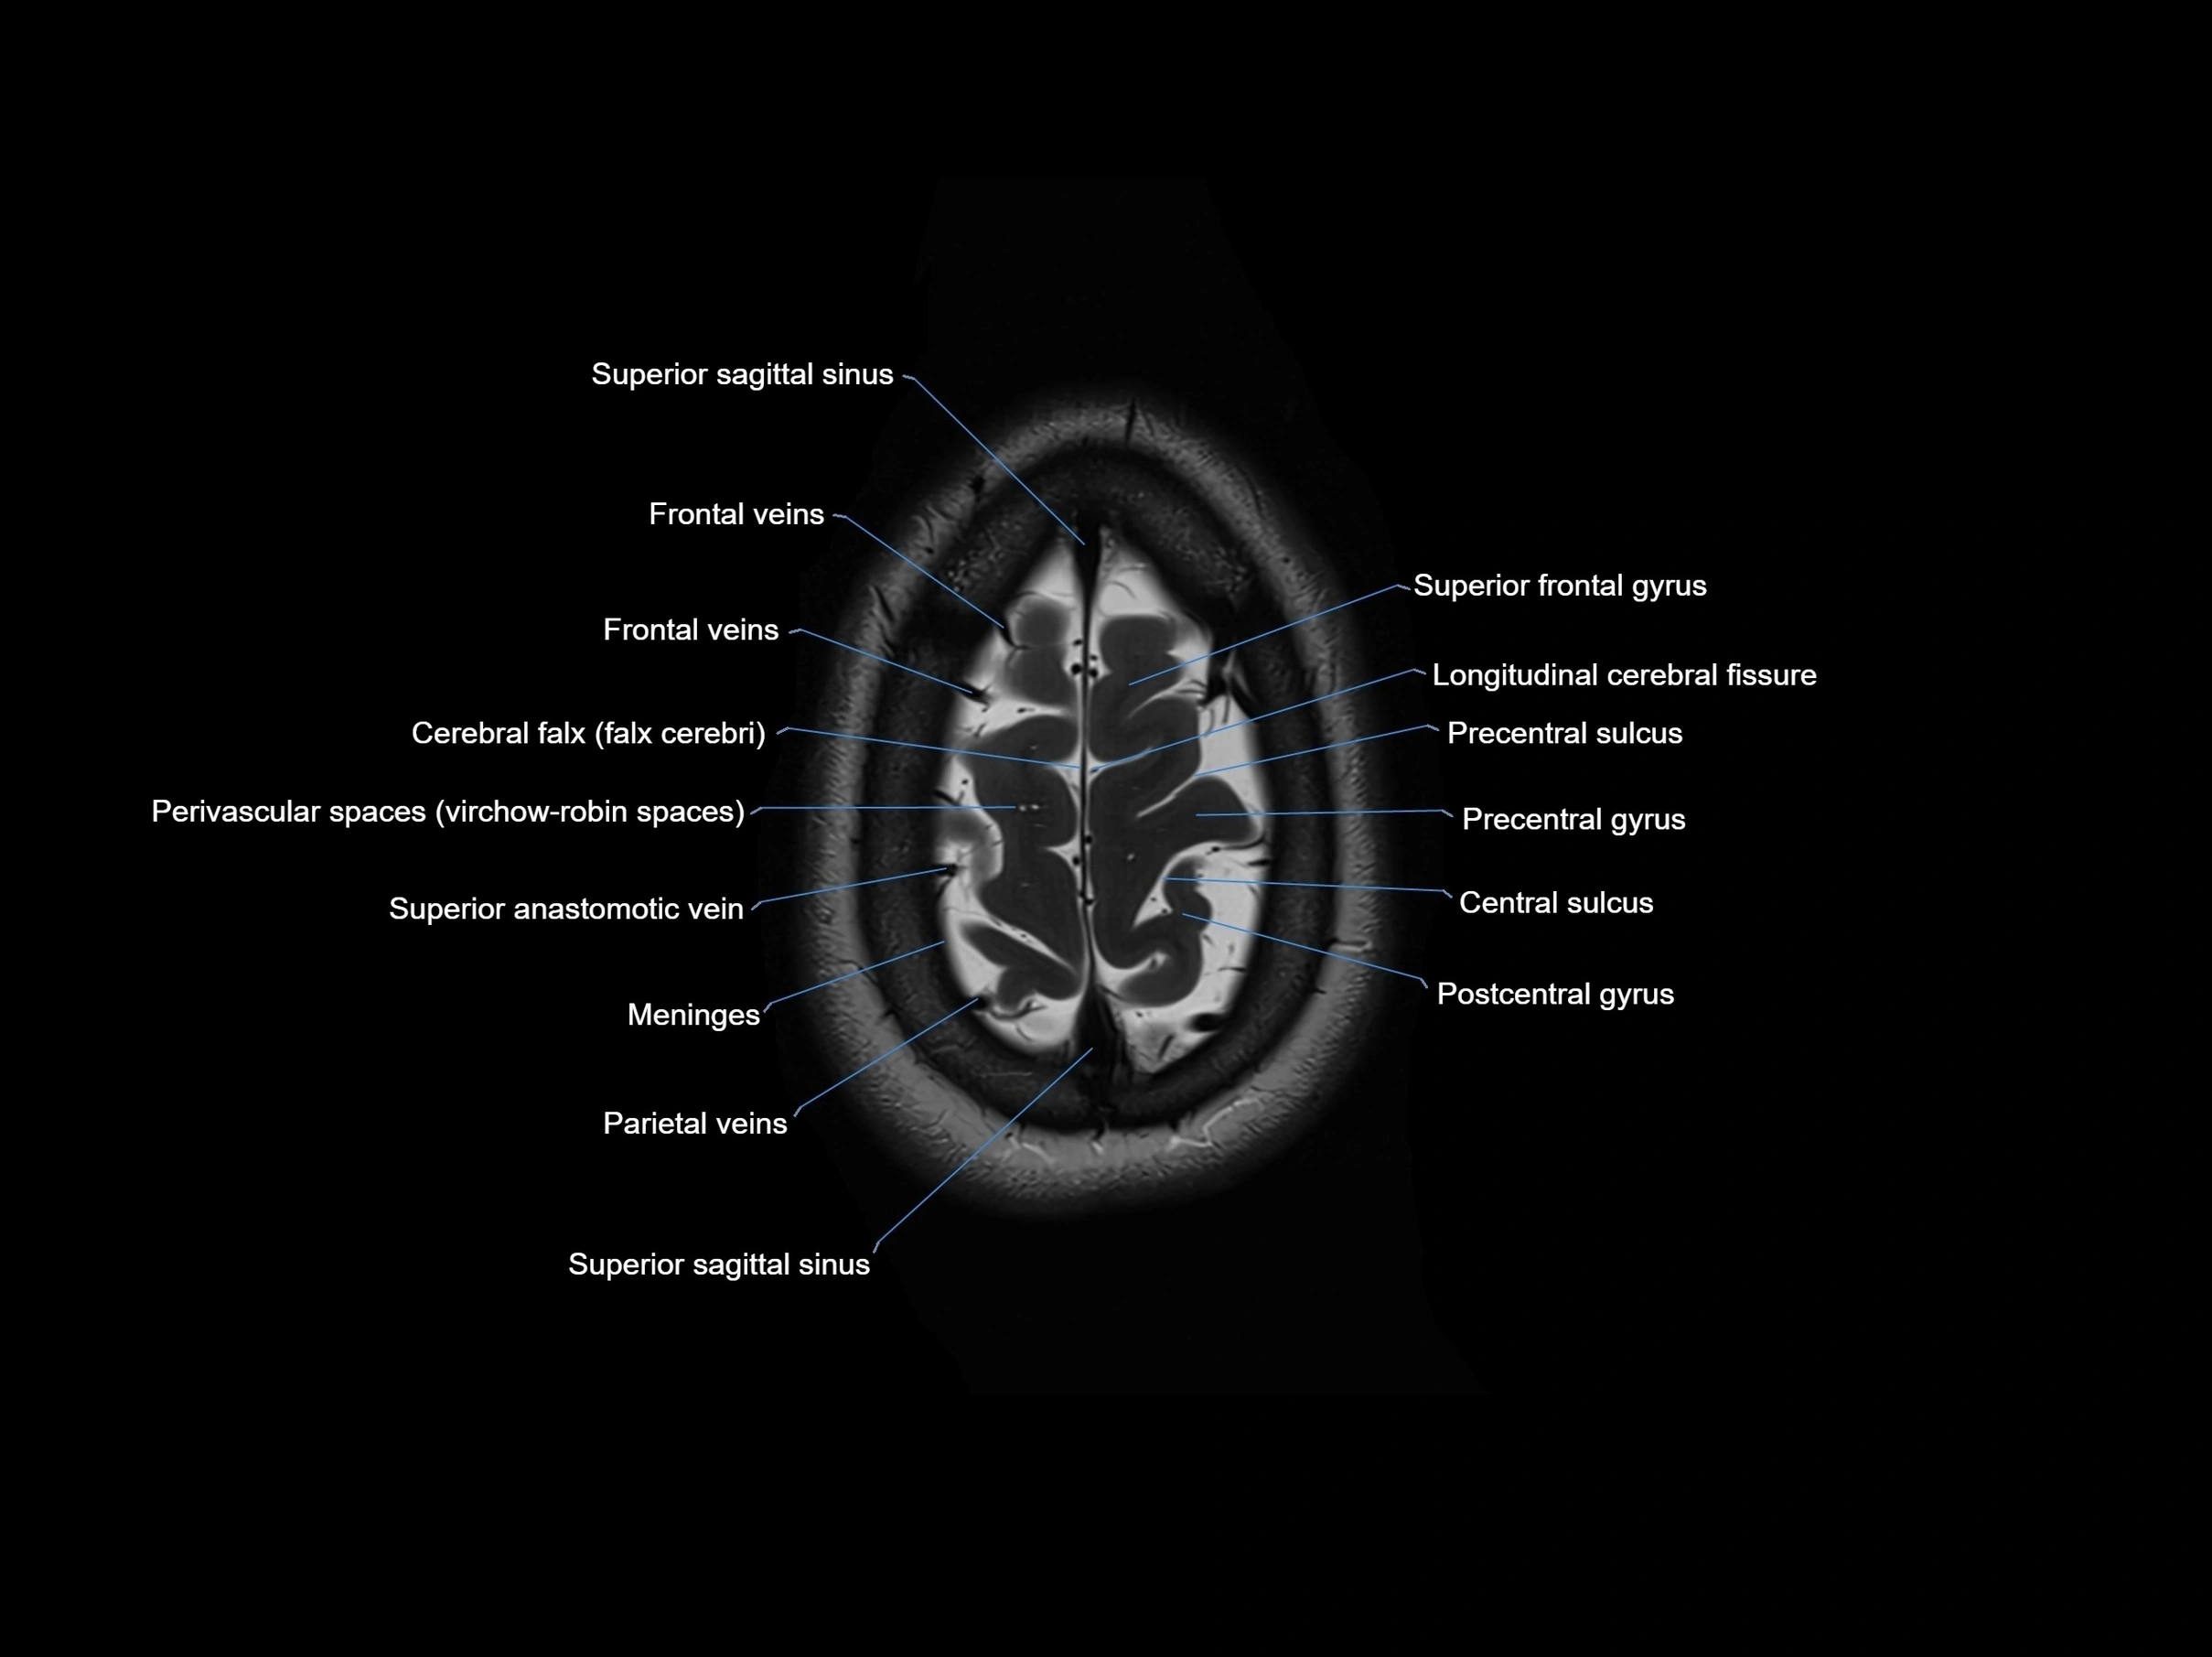

MRI images